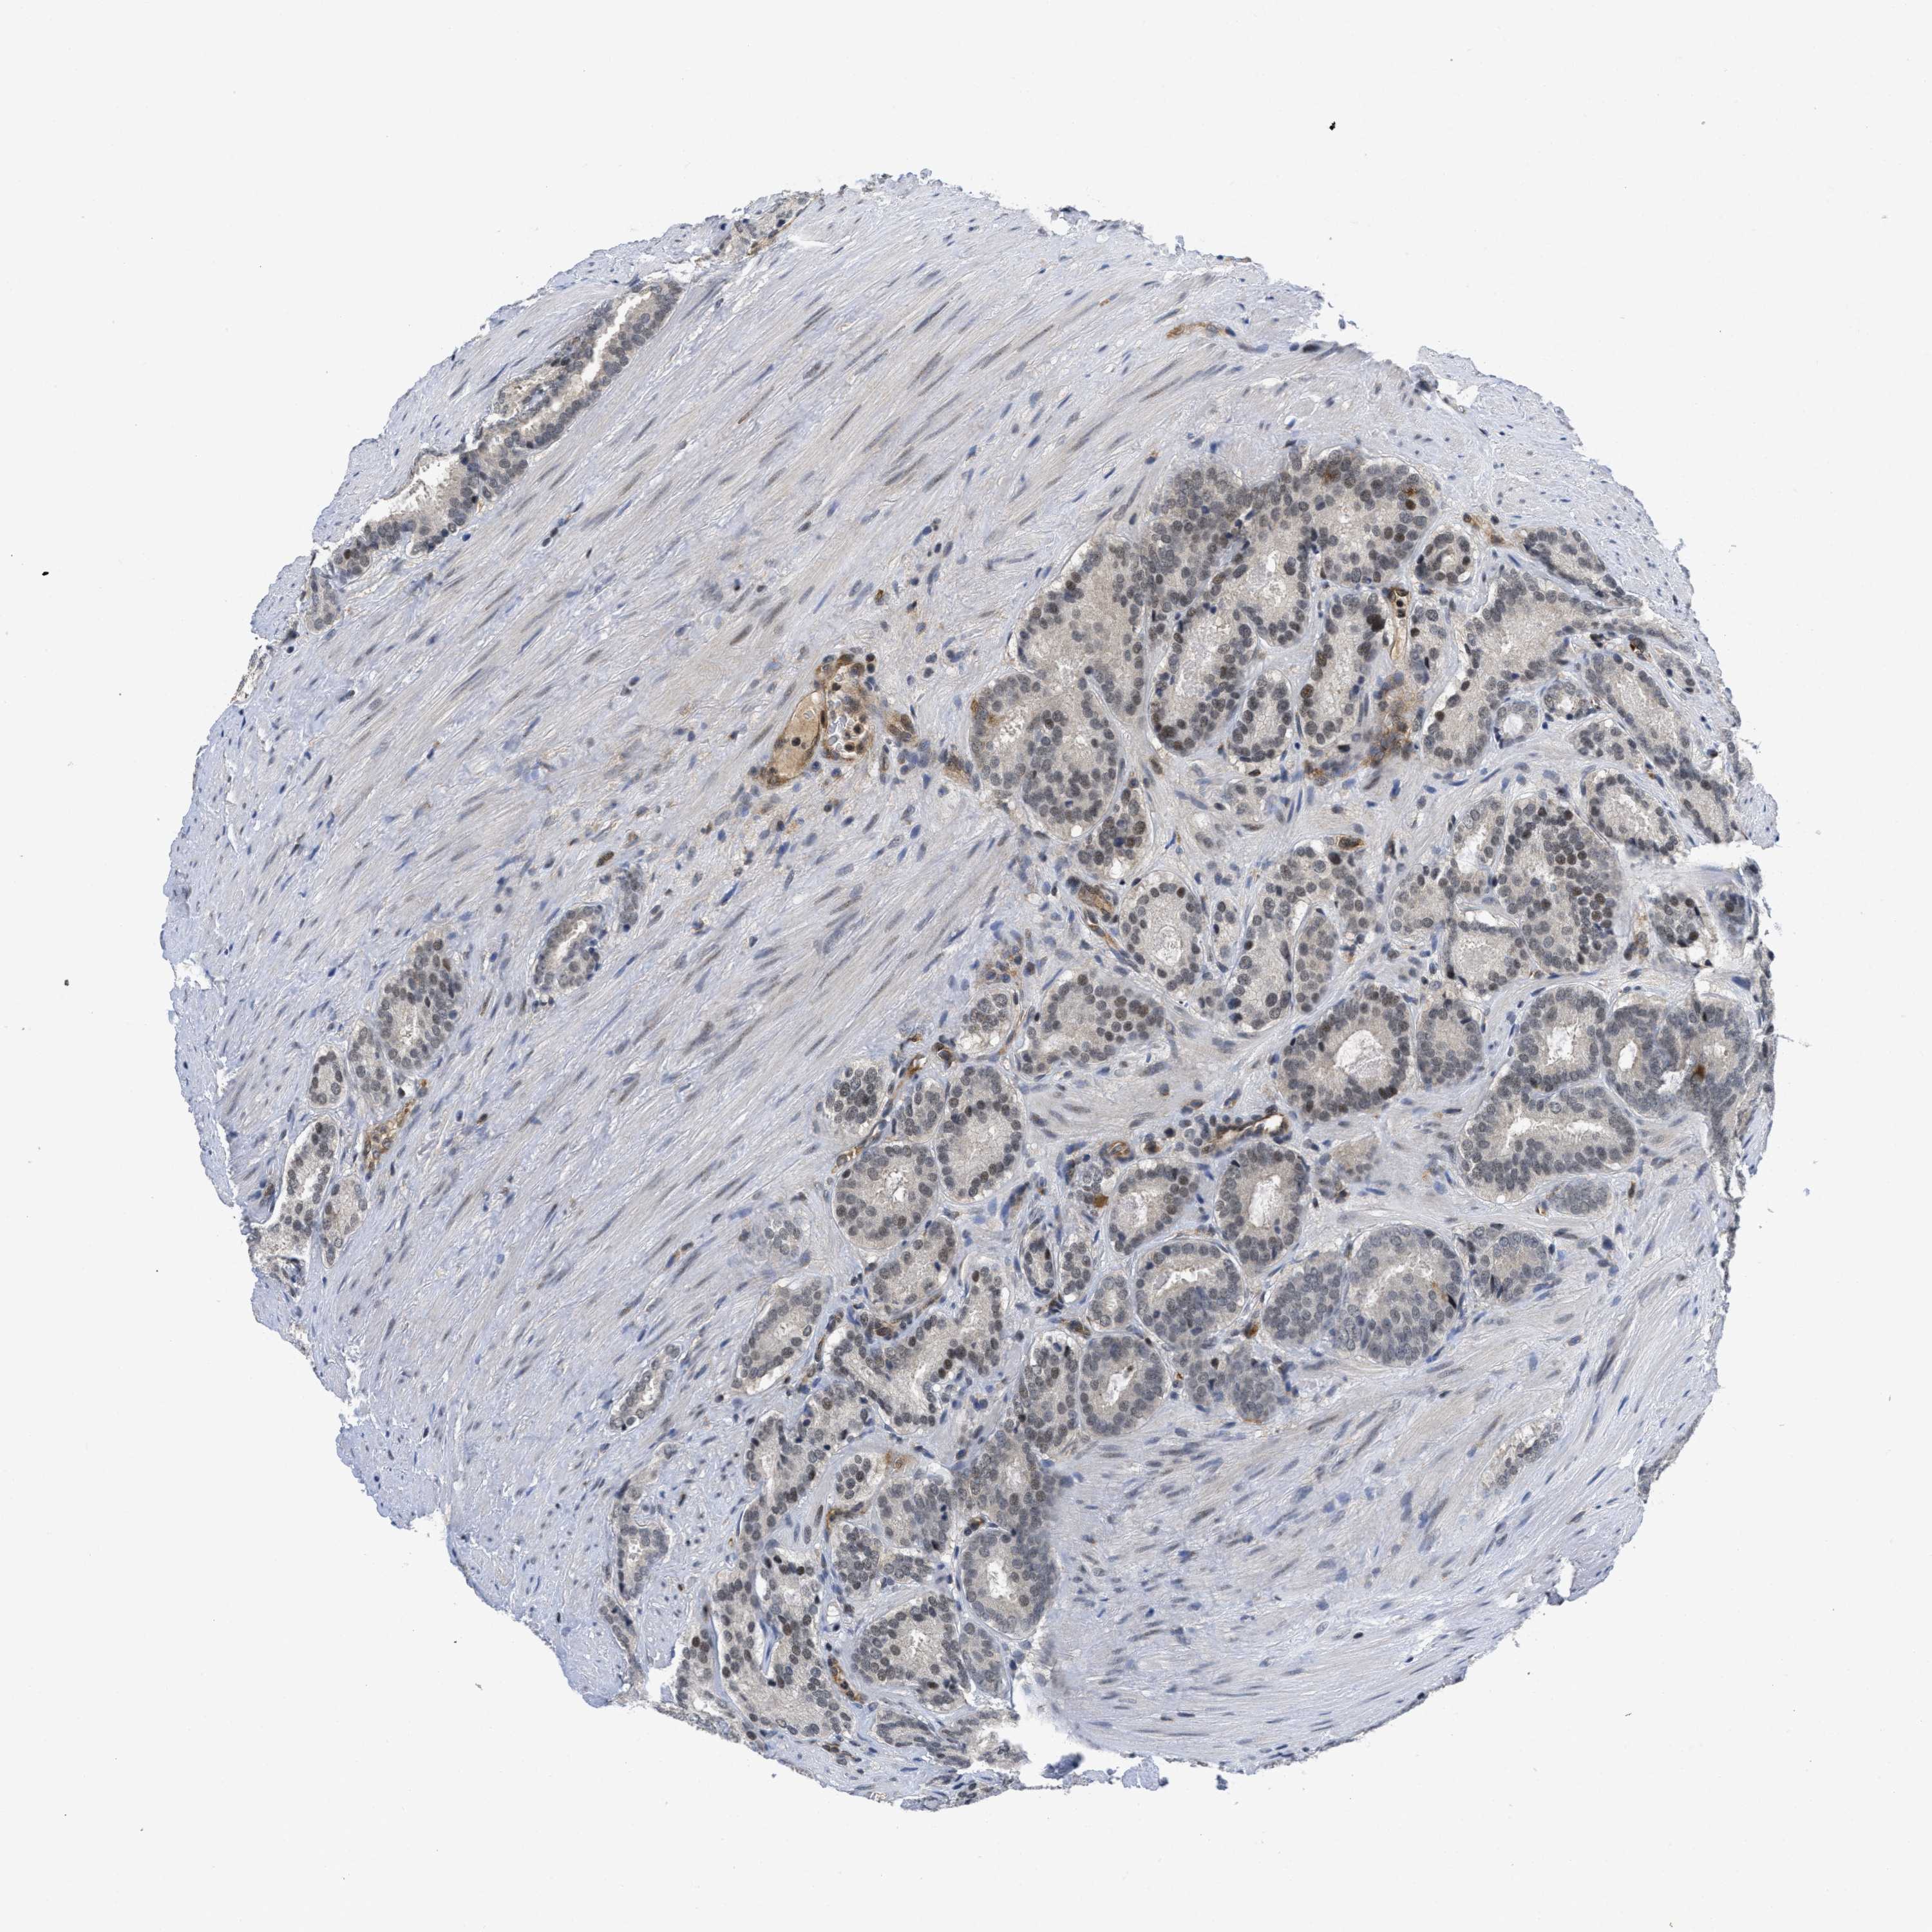

PROSTATE CANCER - Protein expressioni

A mouse-over function shows sample information and annotation data. Click on an image to view it in a full screen mode. Samples can be filtered based on level of antibody staining by selecting one or several of the following categories: high, medium, low and not detected. The assay and annotation is described here.

Note that samples used for immunohistochemistry by the Human Protein Atlas do not correspond to samples in the TCGA dataset.

Antibody stainingi

Antibody staining in the annotated cell types in the current human tissue is reported as not detected, low, medium, or high, based on conventional immunohistochemistry profiling in selected tissues. This score is based on the combination of the staining intensity and fraction of stained cells.

Each image is clickable and will lead to virtual microscopy that enables deeper exploration of all samples and also displays staining intensity scores, fraction scores and subcellular localization as well as patient and tissue information for each sample.

Antibody HPA001275

Antibody CAB017442

Staining

High

Medium

Low

Not detected

Intensity

Strong

Moderate

Weak

Negative

Quantity

>75%

75%-25%

<25%

None

Location

Nuclear

Cytoplasmic/membranous

Cytoplasmic/membranous,nuclear

Adenocarcinoma, Medium grade

Adenocarcinoma, Low grade

Adenocarcinoma, High grade